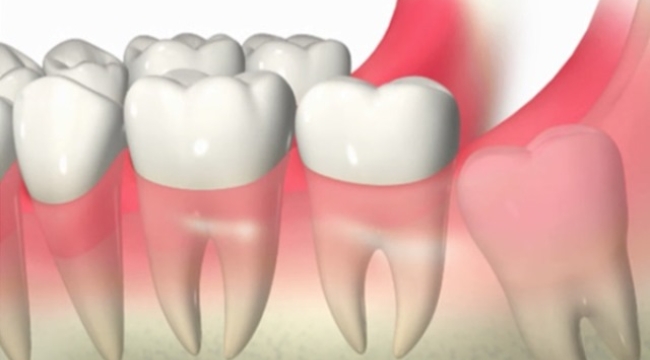

En az 1 dişi eksik 30 erkekte denenecek

Şimdi bilim insanları, benzerliği gerçekten görecek çünkü insanlar da aynı türde bir deneyden geçiyor. 11 ay sürecek bu çalışma, 30 ile 64 yaş arasında, en az bir dişi eksik olan 30 erkek üzerinde yapılıyor. İlacın etkinliğini ve güvenliğini göstermek için damar yoluyla uygulanacak. Şanslıyız ki, önceki hayvan deneylerinde herhangi bir yan etkiye rastlanmadı.

Her şey yolunda giderse, Kitano Hastanesi bu tedaviyi 2 ila 7 yaş arasında, en az dört dişi eksik olan çocuklara uygulayacak.